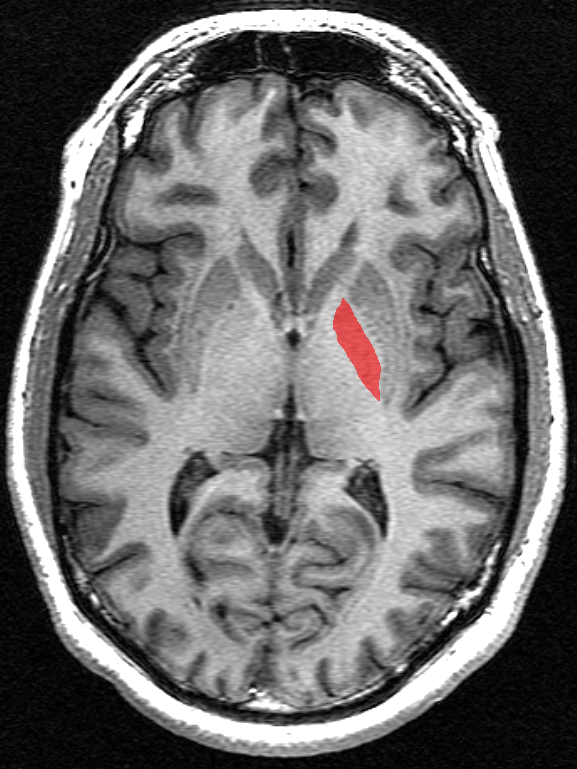

담창구는 기저핵의 일부로, 자발적인 운동 조절에 관여하는 뇌의 구조이다. 얇은 내측 수질판에 의해 내부 담창구와 외부 담창구로 나뉘며, 흑색질 치밀부에서 도파민성 축삭을 받는다. 담창구는 간접 경로 및 직접 경로를 통해 시상으로 정보를 전달하며, 억제적인 영향을 통해 소뇌의 흥분을 조절하여 부드럽고 제어된 움직임을 가능하게 한다. 창백핵 경색, 대사 장애, 신경 퇴행성 질환 등 다양한 질환과 관련되며, 창백핵 절개술, 심부 뇌 자극술 등의 치료법이 사용된다.

영장류의 담창구는 얇은 '''내측 수질판'''에 의해 내부 담창구(GPi)와 외부 담창구(GPe) 두 부분으로 나뉜다.[7] 이들은 모두 수초로 둘러싸인 닫힌 핵으로 구성되어 있다.

담창구는 미상핵과 피각으로 이루어진 선조체로부터 입력을 받아 시상으로 전달한다. 담창구는 내측부와 외측부로 나뉘는데, 내측부는 시상으로 직접 정보를 전달하고, 외측부는 내측부를 거쳐 시상으로 정보를 전달한다.

4. 1. 담창구 외절 (GPe)

영장류에서 담창구는 얇은 '''내측 수질판'''에 의해 내부 담창구(GPi)와 외부 담창구(GPe) 두 부분으로 나뉜다.[7] 이들은 모두 수초로 둘러싸인 닫힌 핵으로 구성되어 있다.

'''담창구 외절'''(GPe)은 '''간접 경로'''의 구성 요소이며, 선조체로부터 GABA작동성 입력을 받는다. 담창구 외절로부터의 GABA작동성 출력은 시상하핵, 담창구 내절, 흑질 망상부로 입력된다.

4. 2. 담창구 내절 (GPi)

영장류에서 담창구는 얇은 '''내측 수질판'''에 의해 내부 담창구(GPi)와 외부 담창구(GPe) 두 부분으로 나뉜다.[7] 이들은 모두 수초로 둘러싸인 닫힌 핵으로 구성되어 있다.'''담창구내절'''(GPi)은 선조체로부터 GABA 작용성 입력을 받는 직접 경로와, 담창구외절로부터 GABA 작용성 입력 및 시상하핵으로부터 글루탐산 작용성 입력을 받는 간접 경로를 통해 입력을 받는다. 흑질 망상부와 함께 대뇌 기저핵의 출력 핵으로 기능한다.